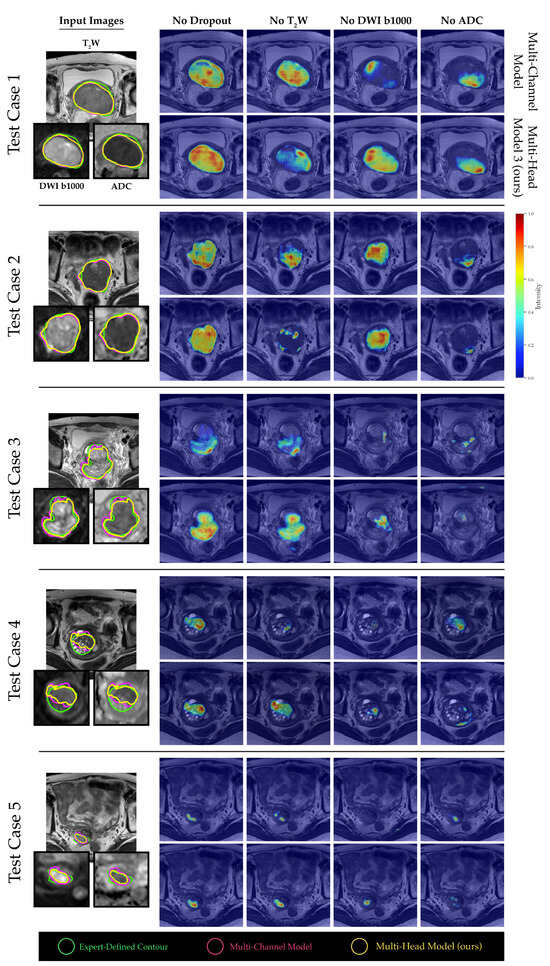

2.4. Channel Sensitivity Analysis and Visualization